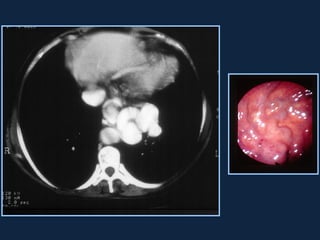

Abscessos Piogênicos

► Coleção localizada de pus no parênquima       hepático

devido a uma infecção bacteriana.

► Origem:

 Infecções intestinais com disseminação hematogênica

secundária (diverticulite)

 Infecções de vias biliares (colangite)

 Extensão direta (vesícula biliar , rim direito...)

 Gram negativos e anaeróbios

► QC: paciente de meia idade a idoso com febre,

desconforto abdominal, hepatomegalia, leucocitose

► Icterícia (40%)

►s/c: Lesão grosseiramente arredondada, hipodensa

(0-45 HU), podendo conter septações e gás (sinal

específico, presente em menos de 20% dos casos).

Pode haver nível ar-fluido e fluido-debris.

►Realce anelar e/ou das        septações   após   a

administração do contraste.

►Pode haver derrame pleural e atelectasia de lobo

inferior direito.

 S/C                 Fase portal

 Fase arterial         Fase portal

 Fase tardia